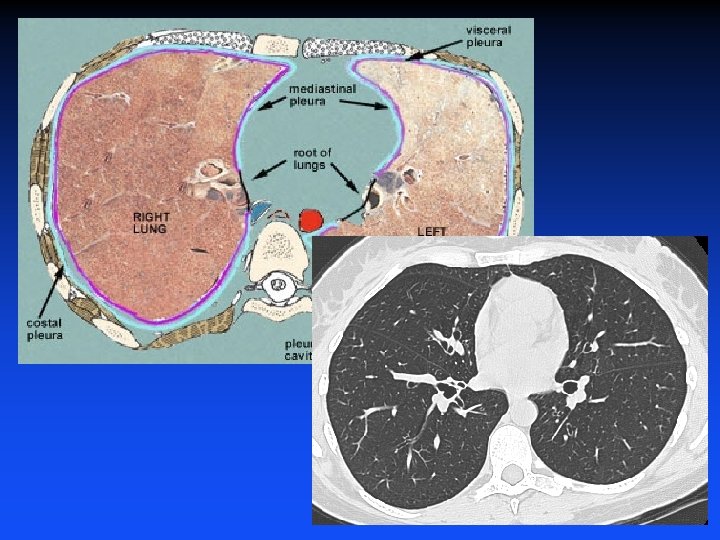

Pleura and Pleural Space

Pneumothorax • Definition: air within the pleural cavity • Source of air: • Lung - most common • Outside air - due to trauma • Hollow visceral organ, e. g. , esophagus

Pneumothorax Diagnosis • Chest radiography or CT demonstrating air in the pleural cavity